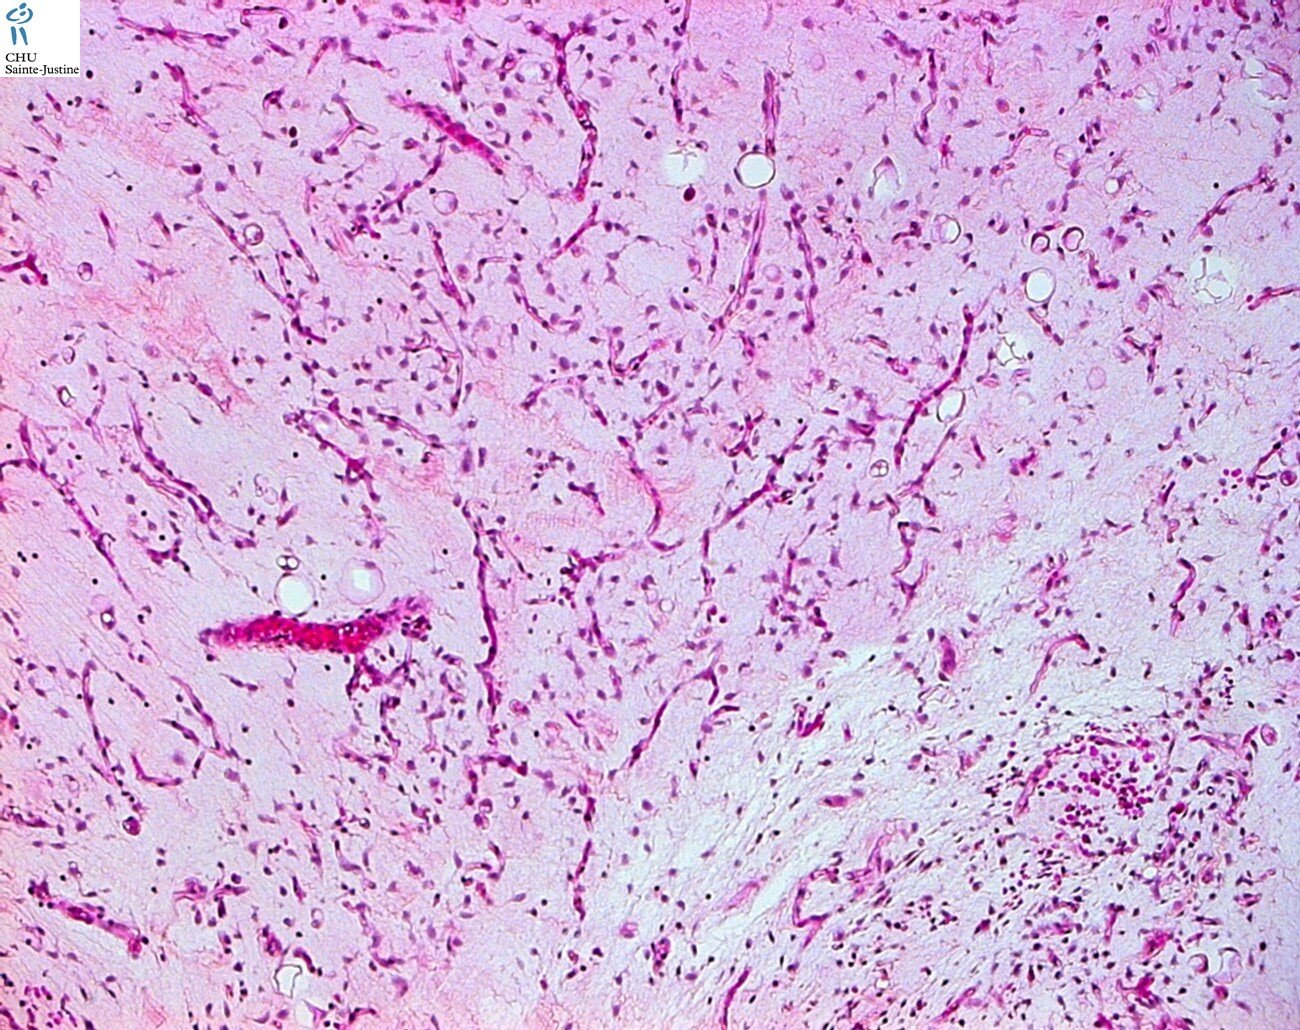

benign adypocytic tumors

| lipoma |

| lipoblastoma |

| lipoblastomatosis |

| well differenciated liposarcoma and atypical lipomatous tumor |

| dedifferentiated liposarcoma |

| myxoid/round cell liposarcoma |

| spindle cell liposarcoma |

| pleomorphic liposarcoma |

| mixed-type liposarcoma |

| liposarcoma |